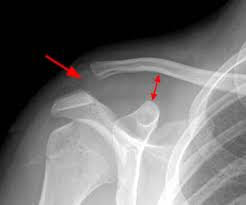

Ανάλογα με το βαθμό της παρεκτόπισης της κλείδας σε σχέση με το ακρώμιο και την κάκωση των συνδέσμων που τη συγκρατούν, ενα εξάρθρημα στην κλείδα διακρίνεται σε 6 τύπους:

- 1ου βαθμού – διάταση των συνδέσμων

- 2ου βαθμού – μερική ρήξη των συνδέσμων

- 3ου βαθμού – ολική ρήξη των συνδέσμων

- 4ου βαθμού – ολική ρήξη των συνδέσμων και παρεκτόπιση της κλείδας προς τα πίσω

- 5ου βαθμού – ολική ρήξη των συνδέσμων και της υπερκείμενης περιτονίας

- 6ου βαθμού – παρεκτόπιση της κλείδας προς τα κάτω

Η διάγνωση γίνεται κατά την κλινική εξέταση του ασθενούς, τη λήψη του ιστορικού και απεικονιστικά με απλές ακτινογραφίες και κατά περίπτωση μαγνητική τομογραφία ώμου. Πάμε να δούμε ποιες είναι οι ενδεδειγμένες θεραπείες ανα περίπτωση ενός εξαρθρήματος κλειδας.